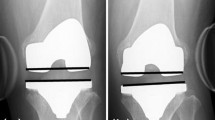

Varus and valgus laxity of the knee in extension (0°), mid-flexion (30°) and flexion (90°) was assessed on radiographs with the use of a custom-made stress device to stress the knee (Fig. 1). Knee laxity was defined as the joint opening under standardized applied moment. The assessments were similar to the method published by Heesterbeek et al. [9]. During the stress radiographs, the subject was in a supine position on a table with the lower leg on a platform with the knee consecutively extended (but unlocked), flexed in 30° and flexed in 90°, with the leg muscles relaxed. The foot was placed in an ankle–foot orthosis. To minimize femur movement when applying torques to the knee, the upper leg was strapped on a thigh support on the medial and lateral sides just proximal to the femoral epicondyles. With the use of 50 N on a pulley 0.30 m distally from the joint line, an external moment of 15 Nm was applied at the knee joint laterally and medially, resulting in varus and valgus stress, respectively. An external moment of 15 Nm was gradually applied to the knee in a standardized way, so that the subject could have continuously relaxed muscles. Under stress, low-dose radiographs (Multidiagnost Eleva, Philips, Best, The Netherlands) were obtained in the anteroposterior view. For each subject, nine low-dose radiographs were made with varus, valgus and no stress (neutral situation) applied, under fluoroscopic guidance with the roentgen ray direction parallel to the tibia joint surface, centred on the middle of the femorotibial joint space.

Varus and valgus knee laxity calculation

The angle between a tangent line on the femur condyles and a line through the deepest tibial joint surfaces was measured on the varus stress, valgus stress and neutral radiographs (Fig. 2). The measurement tool within the radiographic database program (Volume Vision within IntelliSpace PACS Enterprise version 4.4, Philips, Foster City, United States) was used, and measurements were made to the nearest 0.1°. Varus laxity was defined as the difference between the varus stress situation and the neutral situation and valgus laxity, as the difference between the valgus stress situation and the neutral situation [9]. The measurements were performed by a single person (MtM). Duplicates of 25% of the measurements were performed by a second rater (PH), to calculate inter-rater reproducibility. Intra-rater reproducibility was measured with an interval of 4 weeks. Four difficult measurements caused by low-quality radiographs were discussed and scored by consensus of the two raters. For two subjects, the radiographs in 90° flexion were considered to be of insufficient quality, making measurements impossible. These measurements were withdrawn from the data set. Inter- and intra-rater comparisons showed adequate reproducibility for measuring varus and valgus laxity in extension, mid-flexion and flexion in healthy subjects (95% prediction limits (Bland and Altman)) (Table 3). The repeatability of varus-valgus laxity measurements was investigated earlier by Heesterbeek et al. [9] and showed values ranging between 0.6° and 0.9°.